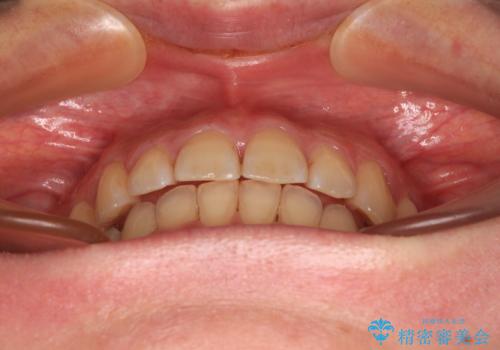

- 上下前歯のデコボコを気にして来院された患者様です。

叢生は軽度で、ワイヤー矯正でもマウスピース矯正でも対応可能な歯列でした。

僅か1年間できれいに歯列を整えることができ、患者様には大変満足していただきました。